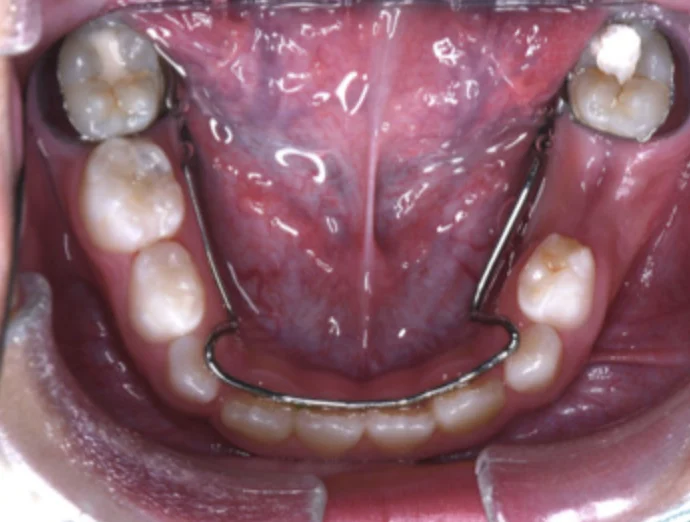

兒童在換牙期出現前牙錯咬時,若能儘早使用簡單的斜面咬合板治療, 百分之90以上的錯咬改正都可得到很好的效果,費用少,且時間短, 若沒在適當時間改善前牙錯咬,會因錯咬影響或限制小朋友顎骨的發育, 提前做一些處理,可以讓小朋友恢復正常的咬合關係, 也會減少將來矯正治療的難度。